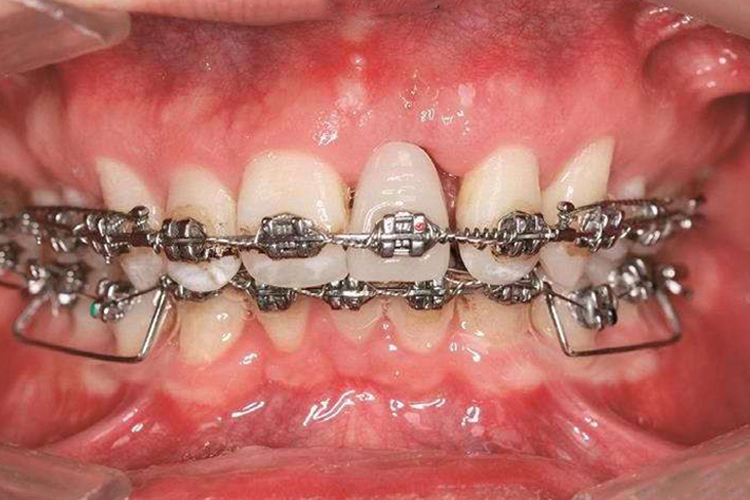

多用途弓一般采用固定矫治器,先矫正内倾的上颌切牙以解除其对下颌的锁结,后使用多用途弓压低下前牙,整平spee曲线,矫正深覆(牙合)。